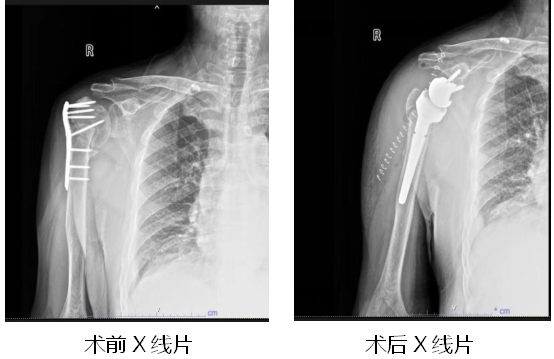

近日,一位60多岁的大爷因右肩关节疼痛,活动受限明显向湖北省第三人民医院(湖北省中山医院)骨外科主任王显勋求助。原来,大约一年前,大爷因外伤致右侧肱骨骨折在外院做过手术,但在恢复期间出现了关节疼痛,活动时疼痛不适。入院经检查判断大爷为“右肱骨头缺血性坏死、右肱骨骨折不连接、右肩关节粘连”。由于患者已在院外进行右侧肱骨骨折钢板内固定术,手术有一定难度,王显勋组织科内进行病例讨论,为患者制定手术方案。在做好充分的术前准备后,王显勋带领副主任黄飞、副主任医师万昌涛等骨科团队为患者行“右侧肱骨内固定装置去除术+反向全肩关节置换术”。术后,护理团队精心指导患者功能锻炼,预防其他并发症发生,患者恢复良好,对治疗效果和护理服务非常满意。

反肩置换术的全称是“反置式人工全肩关节置换术”(RTSA),是指肩关节假体的球形关节面位于肩胛骨关节盂侧,而盂杯位于肱骨近端的半限制性人工全肩关节。